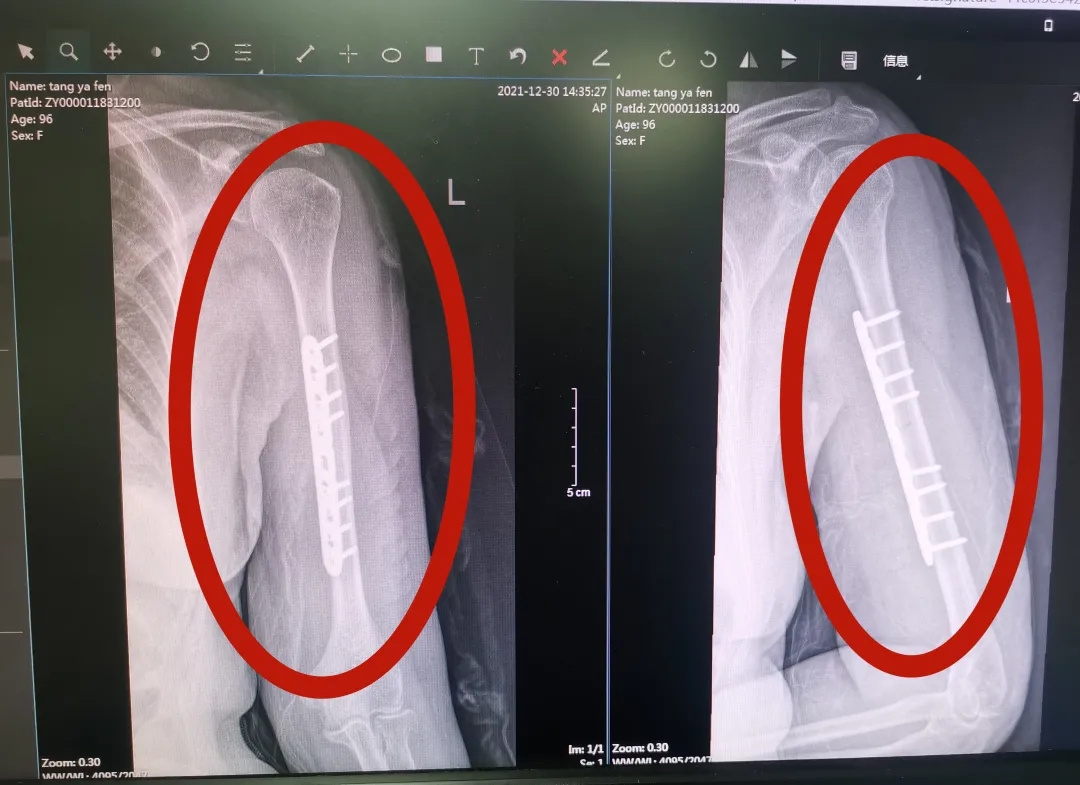

得知唐奶奶能做手术,儿女们都很高兴,但接下来又一个问题横亘在大家面前:唐奶奶患有20多年的高血压合并冠心病,对于手术来说,无疑是一大“拦路虎”。为了保证手术安全,术前,创伤手外科作了充分的准备工作:联系心血管内科专家会诊心血管问题,针对老人年龄大、耐受能力差的特点,创伤手外科又与麻醉科专家联手,为老人做了术前镇痛处理,防止唐奶奶术后因为剧烈疼痛引起围手术期心脑血管意外等。在准备妥当后,唐奶奶才被送上手术台。姚泓成副主任和马昆主治医师主刀,术中,两位专家采用新的手术入路,手术在50分钟内顺利完成,出血量少。

术后,创伤手外科医护团队密切观察唐奶奶的生命体征情况,制定周密的治疗方案,保障围手术期安全,在医护人员的帮助下,唐奶奶术后第2天就能带着前臂吊带下床活动了。此后,姚泓成副主任及马昆主治医生每天到床边亲自指导唐奶奶康复训练,责任护士教给家属和唐奶奶功能锻炼恢复的要领。由于唐奶奶年龄太大,功能锻炼要求的强度很低,康复治疗师手把手一边教一边示范。在医护人员的共同努力下,术后第4天,唐奶奶顺利出院了,她孝顺的子女们都非常感激!

唐奶奶第二次手术后X线检查结果